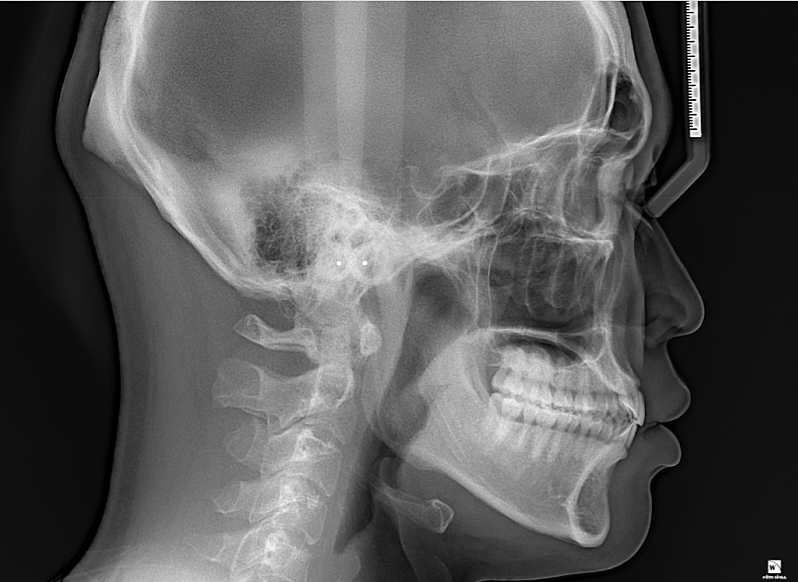

턱이 비율상 대각으로 긴가요?

사진찍으면 턱이 대각으로 긴 느낌과 돌출입 느낌이 있어서 대략적인 판단부탁드립니다

• 1번 째 사진

해당 골격 정도로는 비대칭이라고 보지 않습니다. 너무 예민하게 반응하시는 것으로 보이며 이정도는 정상 범주입니다. 연조직을 보지 않더라도 심미적으로 크게 문제가 되지 않을 것으로 보이며 미세 조정을 원한다면 담당 교정과 선생님과 상담을 해보시길 바랍니다.